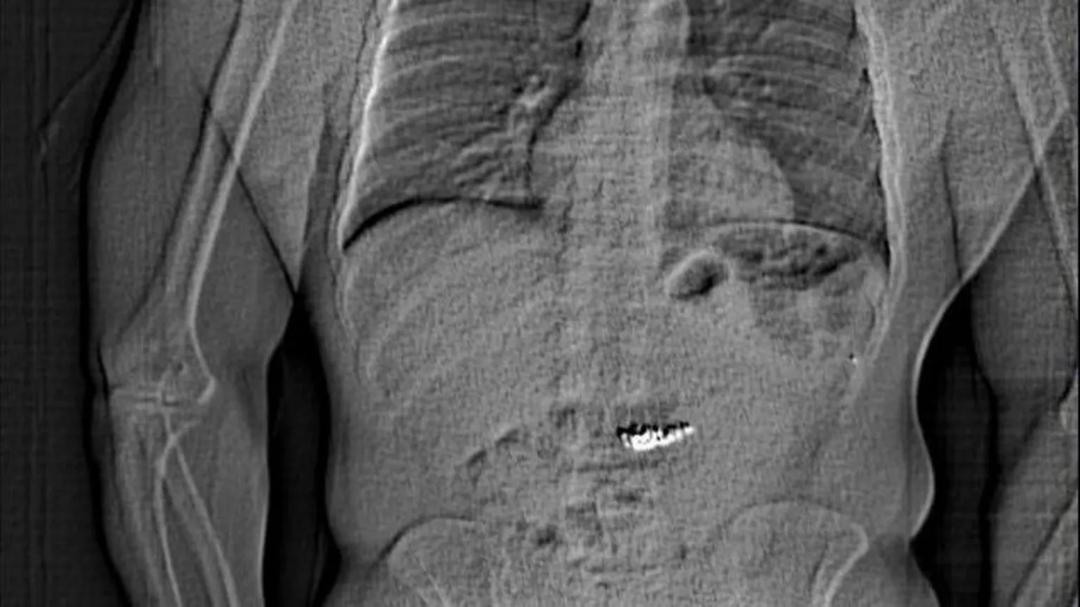

Police later released an x-ray that appeared to show an individual’s abdomen with a foreign object inside.